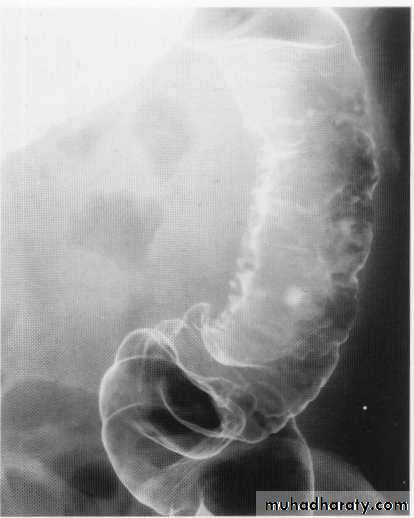

Leiomyoma Ba swallow